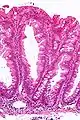

| Micrograph of a sessile serrated lesion. H&E stain. | |

SSLs are diagnosed by their microscopic appearance; histomorphologically, they are characterized by (1) basal dilation of the crypts, (2) basal crypt serration, (3) crypts that run horizontal to the basement membrane (horizontal crypts), and (4) crypt branching. The most common of these features is basal dilation of the crypts.

Unlike conventional colonic adenomas (e.g. tubular adenoma, villous adenoma), they do not (typically) have nuclear changes (nuclear hyperchromatism, nuclear crowding, elliptical/cigar-shaped nuclei).

Low magnification micrograph of an SSL.